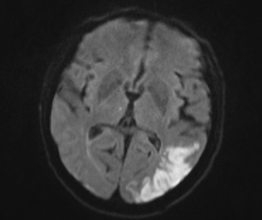

Jenže obraz se často mění a velmi často k horšímu. A u našeho pána se objevily hned dva problémy. Noční zmatenost, neklid, že musel být zklidněn léky, naštěstí nebylo třeba jej kurtovat. Delir. Mysleli jsme zase na alkohol, tedy odvykací stav, ale manželka našeho pacienta to odmítla. Kouřit, to ano, ale alkohol asi ne. K tomu se objevily teploty. A na magnetické rezonanci, kterou skoro u každého nemocného doplňujeme, se objevil takový obrázek. Takže to nebyla taková jednoduchá mrtvice, spíš to vypadalo, že postižená je velká část mozku. Pokud je hodně ložisek mrtvice, je nejčastější příčina v srdci.

Bílá místa jsou areály poruchy prokrvení, tedy mrtvice, v zobrazení DWI na magentické rezonanci.